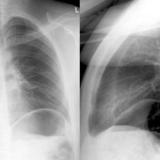

LUL Collapse Case 4 PA and Lateral

Date: 02/19/2004

Views: 3068